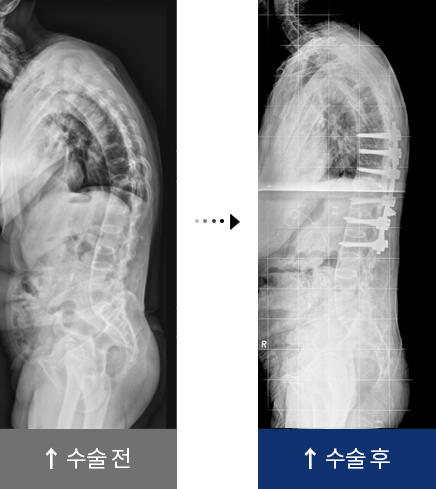

퇴행성 요추 후만증